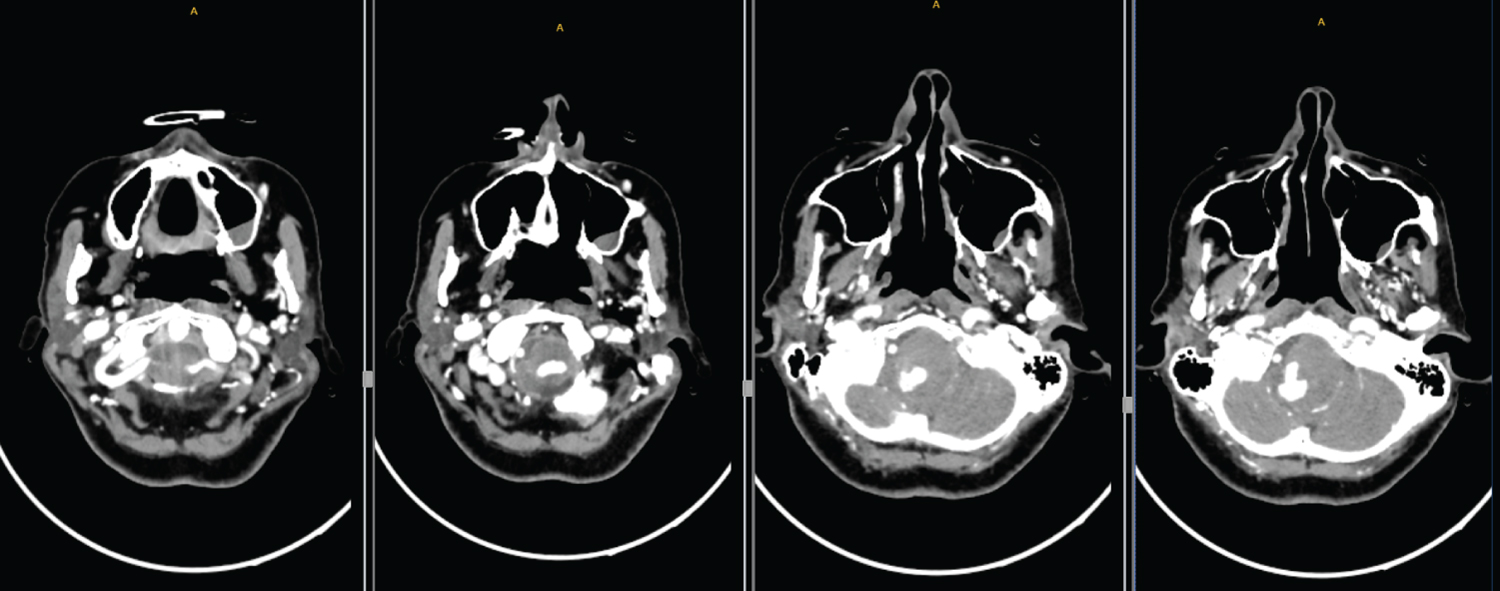

Physical examination was performed before intubation by the E.R. doctor and showed an obvious right slant tongue extension, right sided walking with Medical Research Council [6] grade 5 muscle strength in the right limb and negative bilateral finger to nose and heel to knee tibia tests with normoactive reflexes. After admission to the ICU, the patient underwent digital subtraction angiography (DSA) at Ankara Bilkent City Hospital. A giant spherical aneurysm right vertebral V4 segment aneurysm with a maximum diameter of 30 mm was identified (Figure 2).

Figure 2: A giant spherical aneurysm right vertebral V4 segment aneurysm with a maximum diameter of 30 mm was identified. View Figure 2